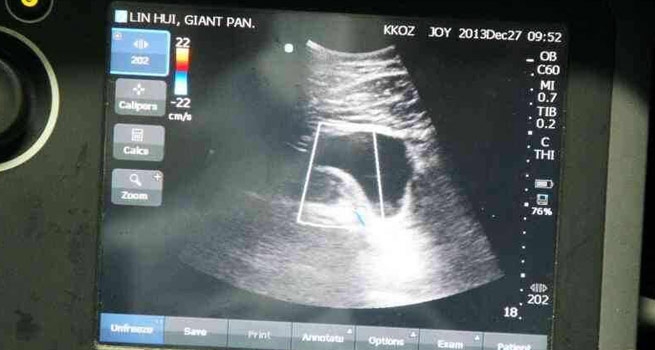

รายงานระบุว่า นายฤทธิณรงค์ กุลประสูตร รักษาการผู้อำนวยการองค์การสวนสัตว์ในพระบรมราชูปถัมภ์ พร้อมด้วยนายกาญจน์ชัย แสนวงศ์ ผู้อำนวยการสวนสัตว์เชียงใหม่ และสัตวแพทย์บริพัตร ศิริอรุณรัตน์ หัวหน้าทีมโครงการวิจัยแพนด้า ได้แถลงผลความคืบหน้าการผสมเทียมแพนด้าหลินฮุ่ยว่า หลังจากทีมสัตวแพทย์ได้ผสมเทียมด้วยการฉีดน้ำเชื้อสดจากช่วงช่วงถึง 2 ครั้ง ในวันที่ 28-29 กันยายนที่ผ่านมา ล่าสุด ทางสัตวแพทย์ได้อัลตราซาวด์พบตัวอ่อนที่ชัดเจน มีถุงน้ำคร่ำ อยู่ภายในมดลูกของแพนด้าหลินฮุ่ยแล้ว ขณะที่พฤติกรรมและความเปลี่ยนแปลงทางร่างกายก็เป็นไปตามลักษณะของแพนด้าที่กำลังตั้งท้อง